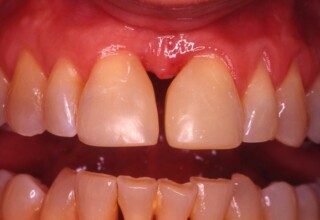

Αποκατάσταση διαστημάτων μεταξύ κεντρικών και πλαγίων τομέων

Τα διαστήματα έχουν δημιουργηθεί κυρίως λόγω των στενών πλαγίων. Μετά την ολοκλήρωση της ορθοδοντικής θεραπείας τα διαστήματα “έκλεισαν” με την τοποθέτηση δύο αποκαταστάσεων σύνθετης ρητίνης.